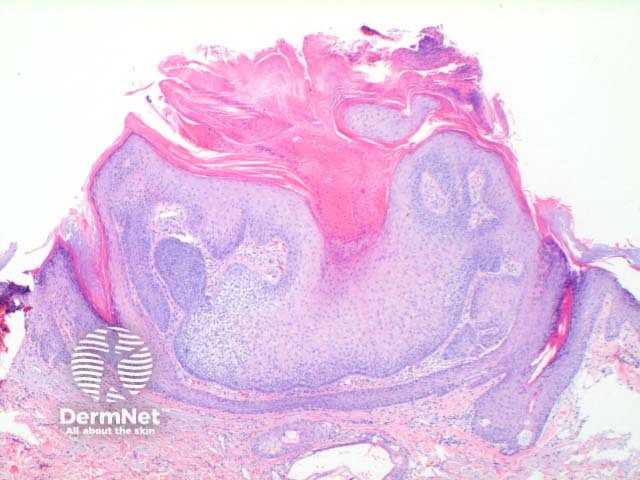

Trichilemmoma is usually a symmetrical epithelial nodular proliferation. Figure 1. There may be mild papillomatosis with overlying hyperkeratosis. Figure 2. The key finding is of a downgrowth of epithelial cells with increasing clear cell differentiation. Figure 2, Figure 3. These changes are frequently more obvious towards the base of the lesion. The clear cell is PAS positive but diastase labile indicative of the glycogen contents. There is often basal peripheral palisading, resting on a distinctive PASD positive eosinophilic hyaline basement membrane. Figure 4.

Figure 1